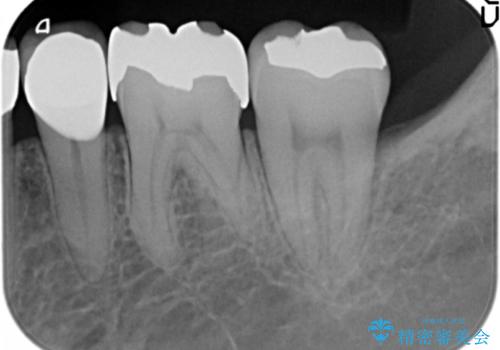

- 奥歯に以前充填した部分に時折知覚過敏があり改善を希望され来院されました。

長期的にみて劣化の早いコンポジットレジンを除去後、しっかりと噛んでいる歯なのでセラミックに比べ壊れたりかけたりすることの少ないゴールドで修復する計画を立てます。

ゴールドインレーは色こそ金属色がでてしまいますが、適合・耐腐食性に優れ壊れることの少ない修復物として理想的な素材です。